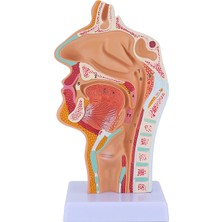

Sant Kuee Burun Boşluğu Boğaz Anatomisi Modeli Insan Anatomik Farenks Larinks Modeli Öğrenciler Için Çalışma Ekranı Öğretim (Yurt Dışından)

Sagrado Burun Boşluğu Boğaz Anatomisi Modeli Insan Anatomik Farenks Larinks Modeli Öğrenciler Için Çalışma Ekranı Öğretim (Yurt Dışından)

Harmonyha Burun Boşluğu Boğaz Anatomisi Modeli Insan Anatomik Yutak (Yurt Dışından)